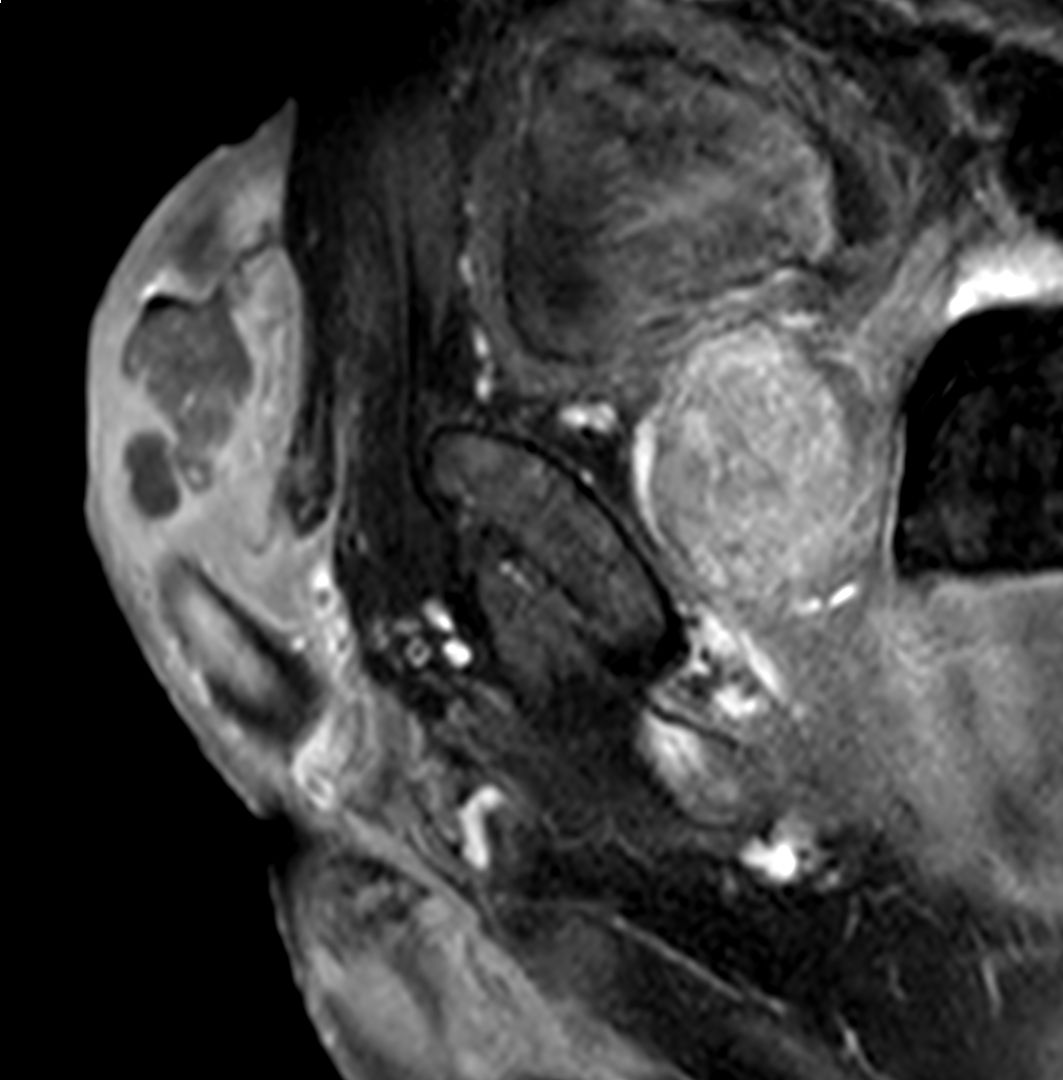

penile cancer photos download

Posts: penile cancer photos download